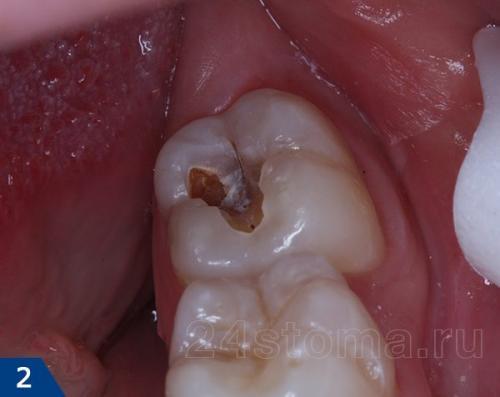

Фиброзный пульпит является одним из типов хронического воспаления пульпы (зубного нерва). Отличительной чертой этого воспалительного процесса является разрастание в образовавшихся при кариесе полостях зуба волокнистых жестких соединительных тканей. Чаще всего пульпит встречается у пациентов старше 20 лет, и в 70% случаев это оказывается именно фиброзный пульпит.

Симптомы фиброзного пульпита

Первым симптомом развития хронического фиброзного пульпита обычно является ощутимая тяжесть в больном зубе. Также болезни свойственны явные болевые реакции на холодное или горячее. Активно зуб может реагировать на металлические или химические раздражители. При недостаточно качественной гигиене ротовой полости пациента и большом скоплении в полостях зуба и десенных карманах остатков пищи, появляется неприятный запах.

При обострении хронического фиброзного пульпита сильная боль в зубах возникает уже самопроизвольно, обычно ближе к вечеру или в ночное время. Но иногда такой пульпит не имеет выраженных симптомов, и обнаруживается только при плановом осмотре у стоматолога. Именно потому важно регулярно посещать врача.